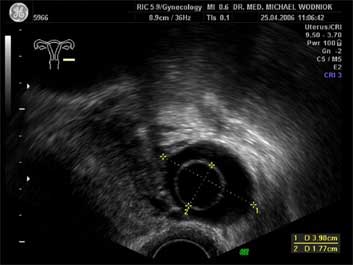

Ultraschall des kleinen Beckens mit der Vaginalsonde Die Ultraschalluntersuchung ist ein bildgebendes Verfahren, welches die Reflektion oder Echos von Ultraschallwellen in den unterschiedlichen Geweben und Organen ausnützt um computergestützt Schnittbilder aus dem Inneren des Körpers zu erstellen. Durch moderne hochleistungsfähige Mikroprozessoren ist es in den letzten Jahren möglich geworden, auch 3-dimensionale oder sogar bewegte 3-dimensionale (4-D) Bilder bzw. Bildsequenzen zu erzeugen. Beides können wir Ihnen in der Praxis anbieten. Eine Ultraschalluntersuchung ist ungefährlich und schmerzfrei. Durch die Anwendung von Dopplerverfahren, mit welchen wir den Blutfluss in den Organen feststellen und messen können, erweitern wir die Untersuchung um die funktionelle Dimension. Ein weiterer Bestandteil unseres Leistungsspektrums ist die farbkodierte Dopplersonographie. Farbkodiert sind entweder die Richtung des Blutflusses oder dessen Intensität. Über die computergestütze Berechnung des Blutflusswiderstandes ist im Einzelnen eine Aussage bzw. Vorhersage über die qualitative und quantitative Durchblutung möglich. (Plazentadurchblutung, kindliche Blutgefässe, Durchblutungsmuster bei verschiedenen Tumoren des Unterleibes und der Brustdrüsen) Ultraschalluntersuchungen haben in unserem Fachgebiet vielfältige Anwendungsmöglichkeiten gefunden. Besonders faszinierend ist der Einsatz im Bereich der vorgeburtlichen Diagnostik. Bereits in der 10. Schwangerschaftswoche ist es möglich, die Extremitäten des Embryos darzustellen und Aussagen zum Körperumrissbild zu machen (Ausschluss von Spaltbildungen, Nackentransparenzmessung). Auch im Bereich der Gynäkologie ist die Bedeutung des Ultraschalls stetig gewachsen und hat sich als erweiterte Vorsorge etabliert. Durch die vaginale Ultraschalluntersuchung können bereits kleine Veränderungen entdeckt werden, die sich der manuellen Tastuntersuchung noch entziehen. Auffällige Tastbefunde an den Eierstöcken sind durch den Einsatz von 3D / 4D in Kombination mit der Farbdoppleruntersuchung besser interpretierbar und können dadurch Frauen unnötige abklärende Operation ersparen. Die Anwendung des 3D Ultraschall, insbesondere im Coronarschnitt, lässt eine effektive Beurteilung für Veränderungen (Polypen, Karzinome) der Gebärmutterschleimhaut zu. ![]() ![]() ![]() ![]()